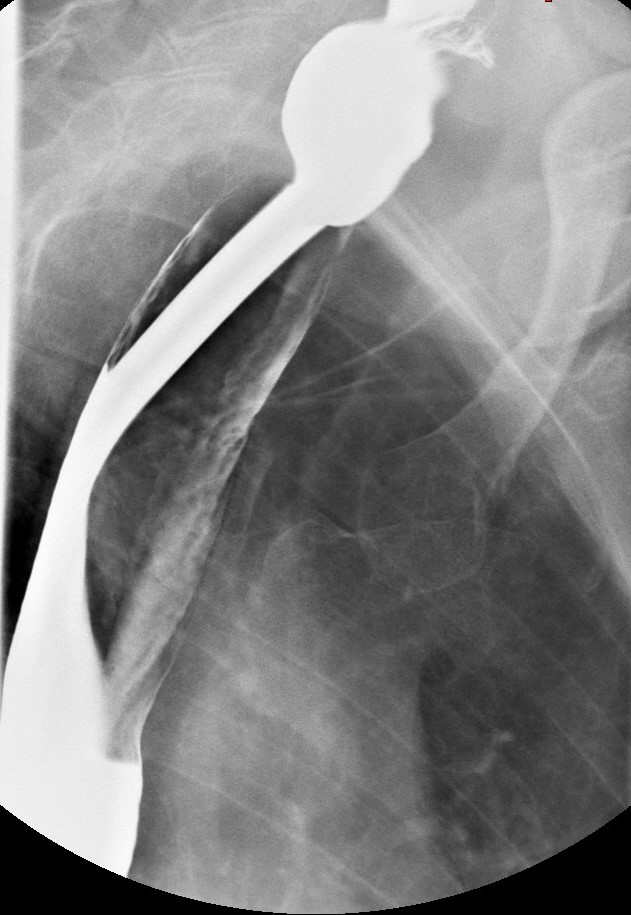

연속적인 조영 위장관 방사선 촬영이나 상부 위장관 내시경 검사를 통해 식도 웹의 존재를 확인할 수 있다.[3] 혈액 검사에서는 철 결핍성 빈혈과 일치하는 저색소성 소구성 빈혈이 일반적으로 나타난다. 영향을 받은 점막의 생검에서는 상피 위축(수축)과 다양한 정도의 점막하 만성 염증이 나타나는 것이 일반적이다. 상피 이형성증 또는 이형성증이 나타날 수도 있다. 어떤 경우에는 이 증후군이 윤상 연골 후 악성 종양으로 나타날 수 있으며, 후두 연골 마찰음의 부재로 감지할 수 있다.

바륨 식도 조영술과 비디오투시경 검사는 식도 웹(esophageal webs)을 감지하는 데 도움이 될 수 있다. 식도 위 십이지장 내시경 검사는 이러한 웹의 육안적 확인을 가능하게 하며, 이는 상피하 섬유증에 의해 발생한다.

바륨 식도 조영술과 비디오투시경 검사는 식도 웹(esophageal webs)을 감지하는 데 도움이 될 수 있다. 식도 위 십이지장 내시경 검사는 이러한 웹의 육안적 확인을 가능하게 하며, 이는 상피하 섬유증에 의해 발생한다.5. 4. 조직 검사